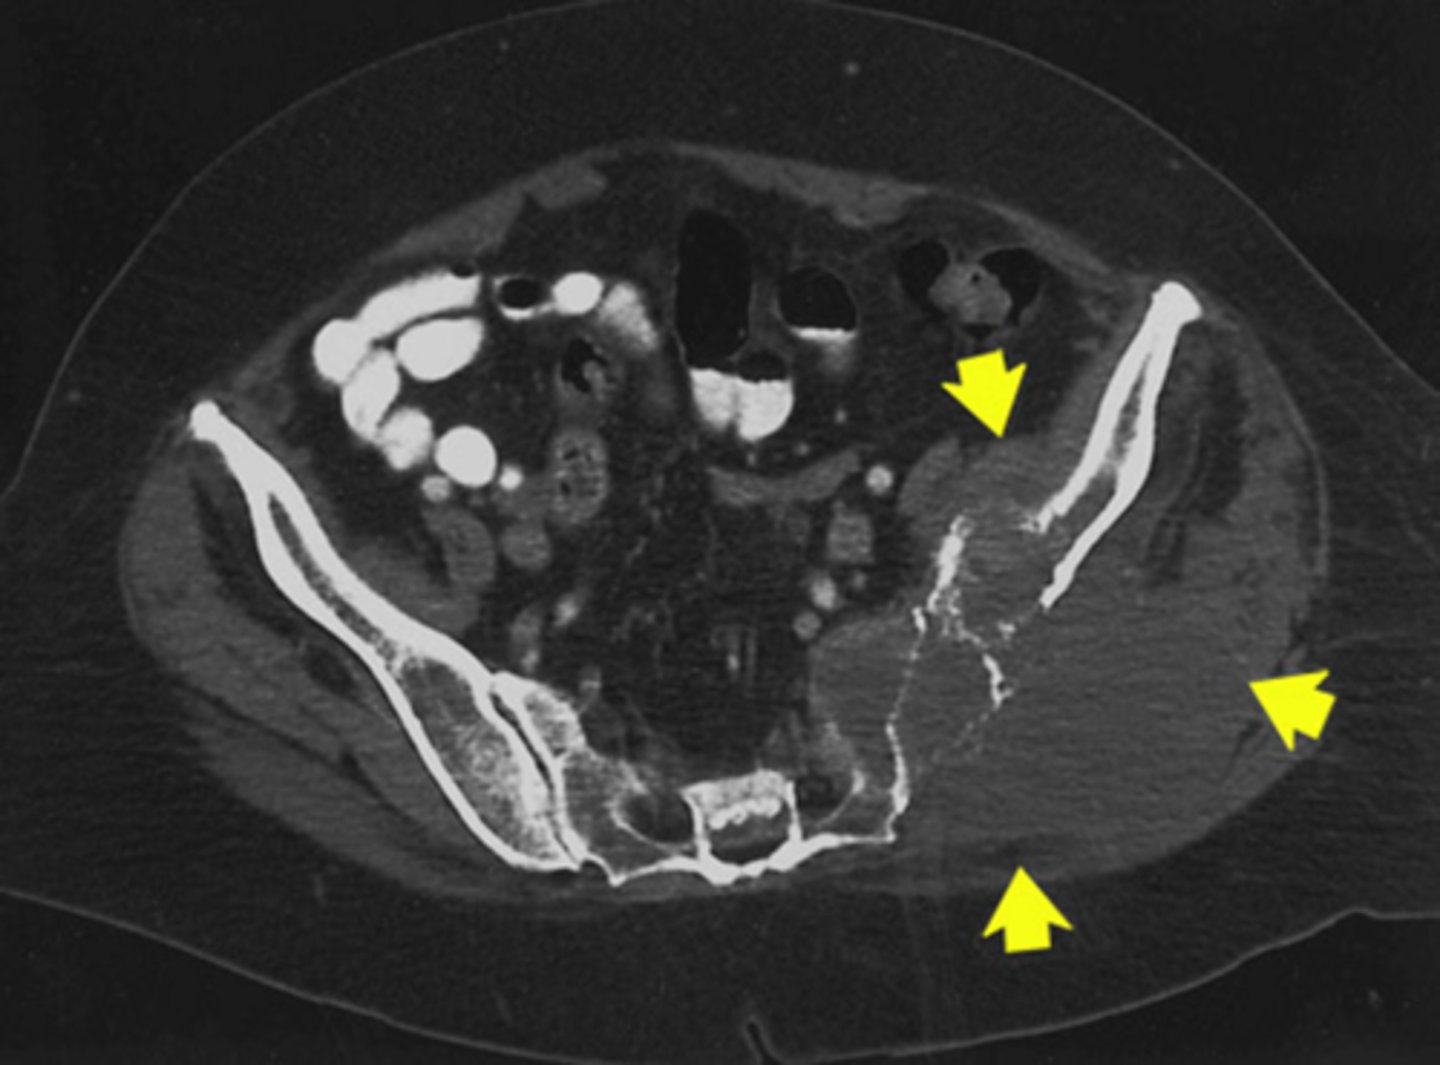

Additive

What kind of pathology is osteosarcoma

Additive

What kind of pathology is present in this image

Multiple myeloma because its widespread

Name the pathology and how can you tell

Heterotopic ossification/ calcification

Name the pathology

Bone growth outside of normal areas

Define heterotopic ossification/ calcification

1) Traumatic injury

2) Surgery

How can a heterotopic ossification/ calcification occur (2)

72 hours

How long do you have to wait after surgery to treat a heterotopic ossification/ calcification with XRT

7 Gy

1 Fraction

What is the typical dose and fractionation of a heterotopic ossification/ calcification